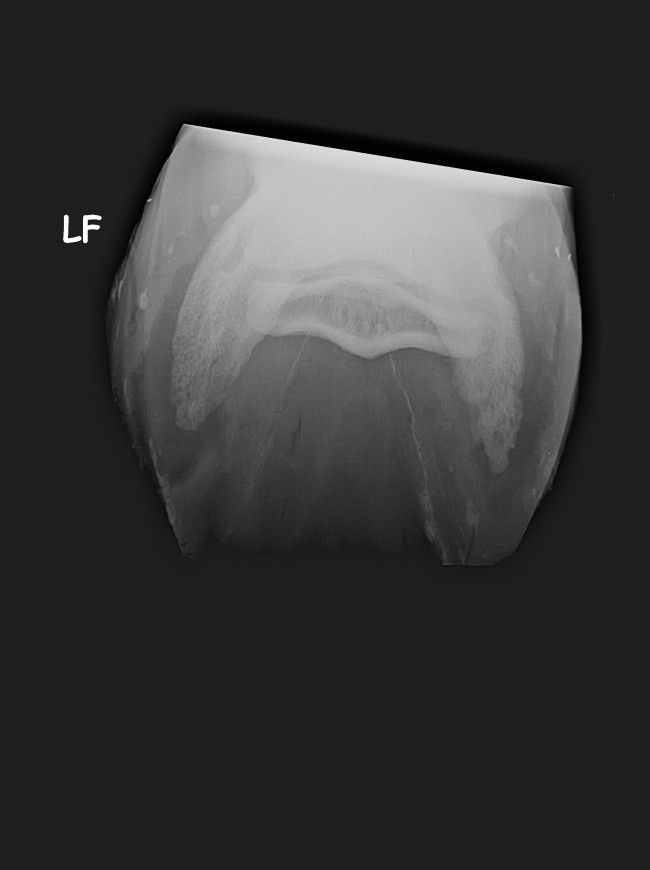

| Dire merci | Voici les premières radios de mon cheval de sa maladie antérieur droit ![]() ![]() |

| Dire merci | premieres radios antérieurs gauche![]() ![]() ![]() |

| Dire merci | les premières radios sont de juillet 2012 Voici les radios de l'antérieur droit fin septembre 2012 ![]() et celles de l'antérieur gauche ![]() ![]() |